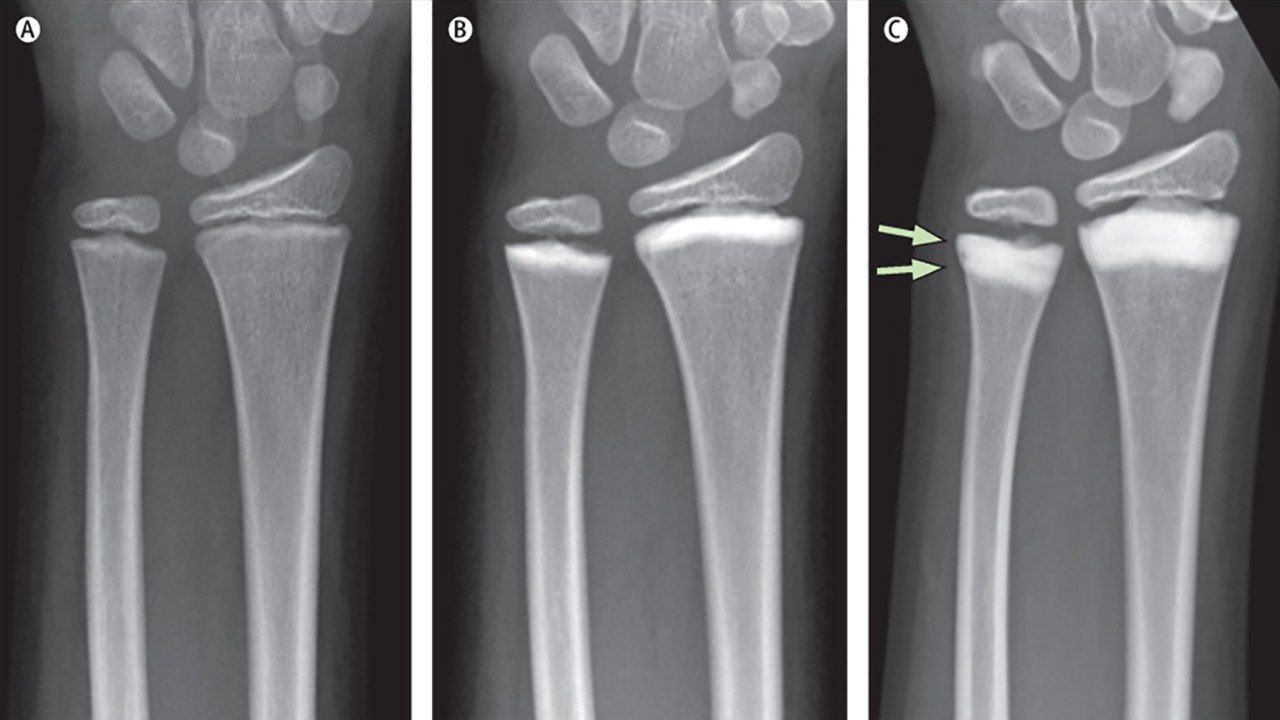

Проверенный метод диагностики – рентгенография сустава в двух стандартных проекциях. Она поможет визуализировать сужение суставной щели, костные выросты, остеопороз и остеосклероз (участки пониженной и повышенной плотности костной ткани, рис. 3).

Рисунок 3. Рентгенограмма правого запястья. Развитие остеопороза (b, c) в ходе лечения с помощью человеческих моноклональных антител. Стрелками отмечены двухслойные склеротические полосы после двух курсов препарата. Источник : Elsevier Ltd/The Lancet